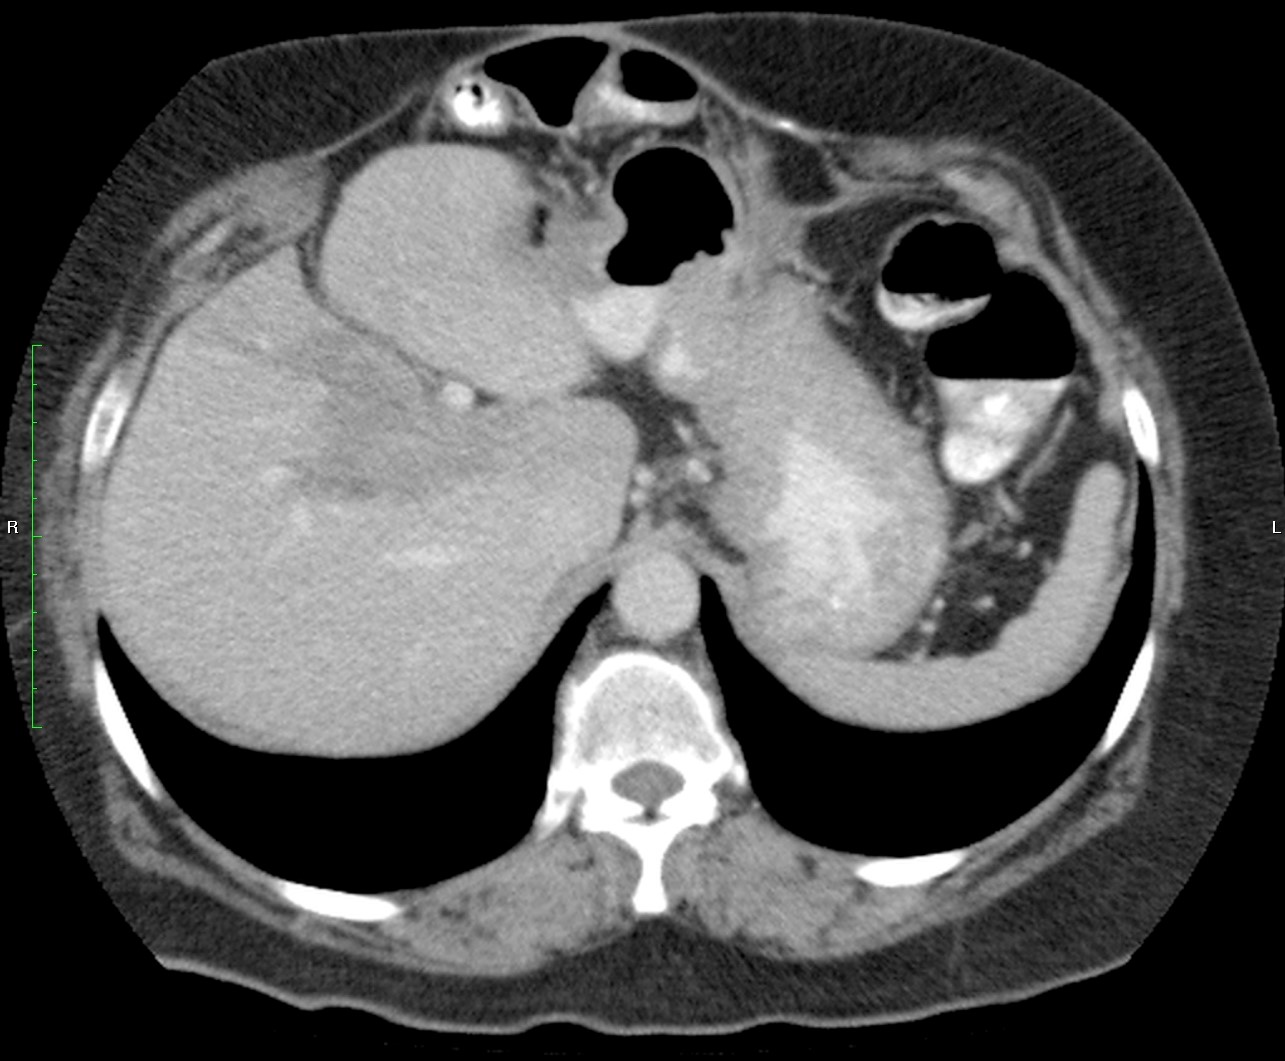

Mujer de 57 años.

Cuadro clínico de 1 mes de evolución caracterizado por distensión abdominal e hiporexia.